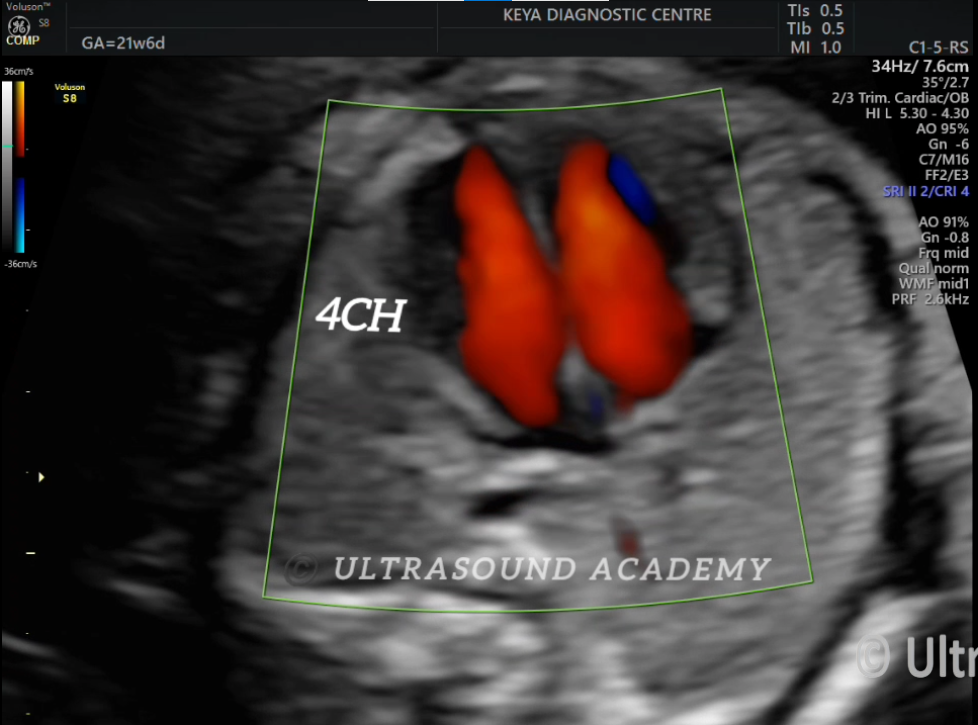

NORMAL FETAL HEART 21 WEEKS

On colour doppler nice evaluation of 4 chamber, LVOT, RVOT, 3 vessel, 3 vessel trachea and aortic arch view along with good depiction of pulmonary veins.